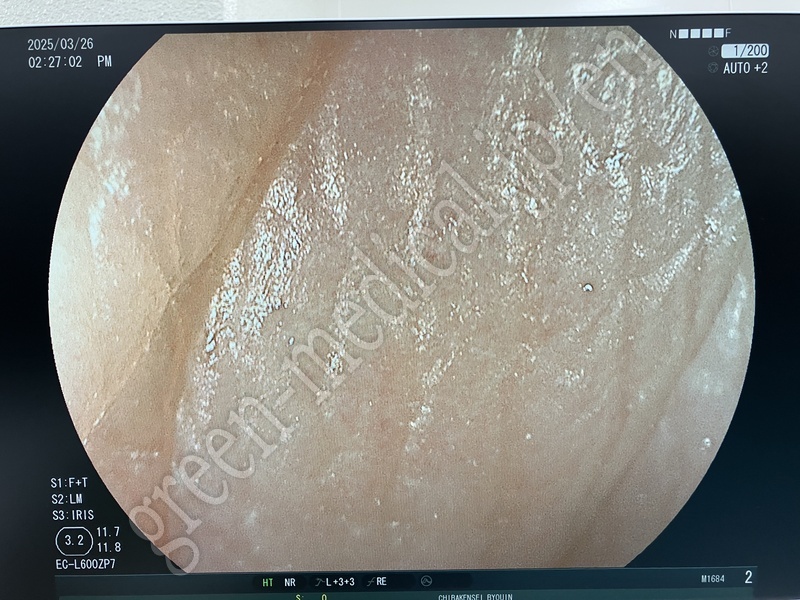

EC-L600ZP7